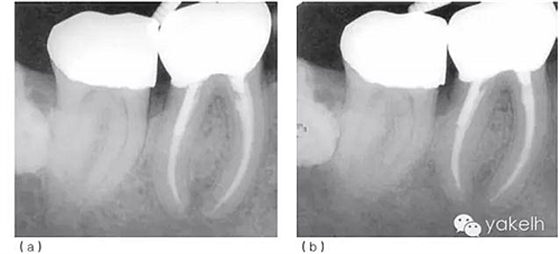

圖5.1.2(a)46根管再治療前X線片。現(xiàn)有修復(fù)體、核及兩個不銹鋼樁均已安全拆除,患牙用不銹鋼帶環(huán)和Ketac-SilverTM臨時修復(fù),這為后續(xù)治療提供了無微滲漏且穩(wěn)定的局部環(huán)境。(b)46根管再治療后X線片。與圖5.1.1相比,根管預(yù)備和充填更接近理想的工作長度,致密度更高。

術(shù)后觀察愈合情況。最后制作新的樁冠。術(shù)后2年、6年復(fù)查,X線片顯示根尖周病損逐漸恢復(fù)(圖5.1.3)。

圖 5.1.3(a)根管再治療后2年復(fù)查,X線片顯示46根尖周骨重建、遠中根管內(nèi)金屬樁、金合金冠修復(fù)。(b)根管再治療后6年復(fù)查,X線片顯示46根尖周完全恢復(fù)。